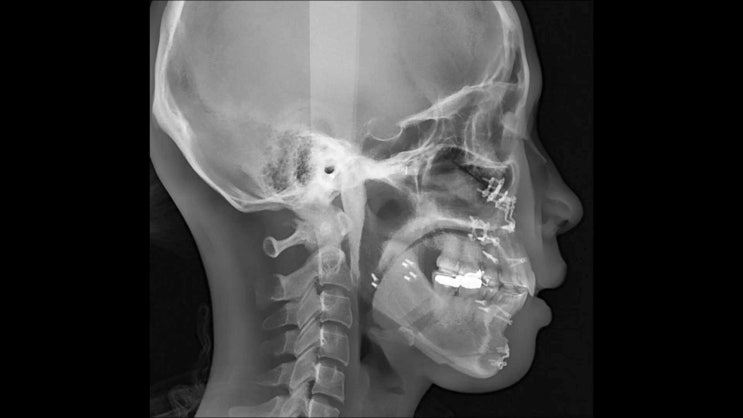

最初の副作用は

当然、下顎の感覚消失です。

両顎手術後に

下顎感覚が落ちる原因である

下歯槽神経損傷を予防する手術方法

すなわち

MANUAL TWIST TECHNIQUE

に関する論文です。

출처: Is injury to the inferior alveolar nerve still comm on during orthognathic surgery? Manual twist techni que for sagittal split ramus osteotomy British Journal of Oral and Maxillofacial Surgery 56(1 0): 946-951, 2018

上の写真のように

MANUAL TWIST TECHNIQUEを

利用して両顎手術を行うと

下歯槽神経損傷という副作用を

予防できるという論文です。

この新技術により

下歯槽神経損傷は

0.1%まで引き下げたという

内容の論文です。